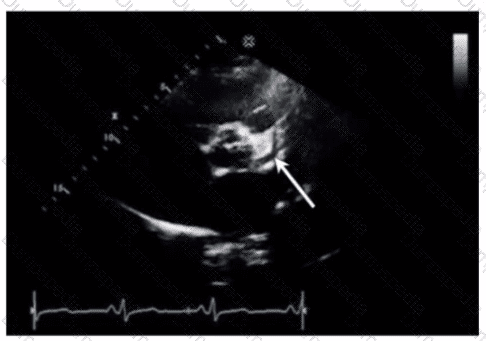

Which region of the aorta is being measured to assess the critical finding in this image?